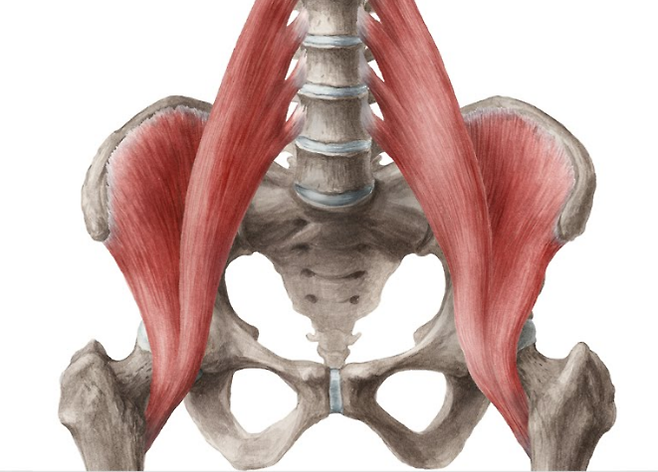

장요근(iliopsoas)은 요추 1~4번의 횡돌기에서 출발하는요근(psoas muscle)과 골반 앞쪽 장골 전체에 붙어서 출발하는 장골근(iliacus muscle)이 만나서붙여진 이름입니다이 두 근육은 같이 만나서 대퇴골의 소전자에 붙죠~

기본적으로 장요근의 수축시 역할은다리를 구부리거나 허리를 피거나 구부리는 역할, 또 다리를 외회전시킨다고 알려져 있습니다.

하지만 정말 중요한 역할은사진속 줄이 양쪽으로 당겨 높은 기둥이 당겨짐의 장력으로 압박받아 고정되는 것처럼요추 바로 옆에 붙어있어서 척추에 적절한 압박(compression)과 전단(anterior shear)력을줘서 허리에 안정성을 제공하는 역할을 하는 것입니다.우리가 푸쉬업, 플랭크 같은 운동을 할때도복근과 같이 척추 안정성을 제공하는 아주 중요한 근육입니다~하지만 어느 것이나 그렇지만 근골격의 문제는한쪽의 너무 과도한 사용으로 균형이 깨졌을때 발생합니다~